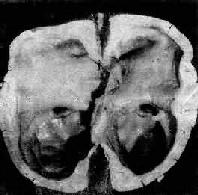

图16-9 脑积水

侧脑室高度扩张,脑组织受压萎缩变薄